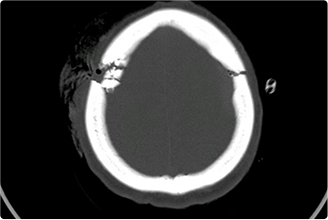

擅长脑血管病(出血与缺血)的神经介入与微创手术,能熟练开展脑外伤、重度颅脑损伤的救治工作。